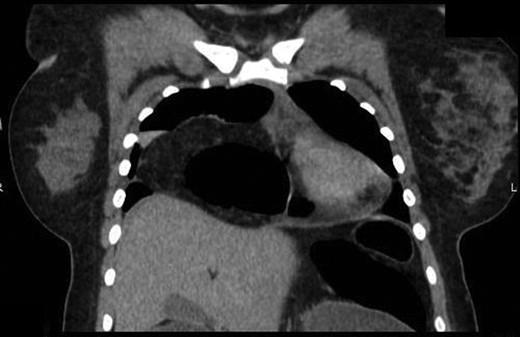

An 18-year-old otherwise healthy female patient presented to a local community hospital emergency department with a 3-day history of non-specific abdominal pain. While at the referring facility, the patients’ pain progressed rapidly to peritonitis. Initial evaluation at the referring facility included a CT scan, which demonstrated herniated large bowel into her thoracic cavity through a suspected anterior/retrosternal hernia (Fig. 1). The patient was transferred to our institution for further management.

Coronal view of herniated colon on computed tomography scan obtained at the referring facility prior to transfer.